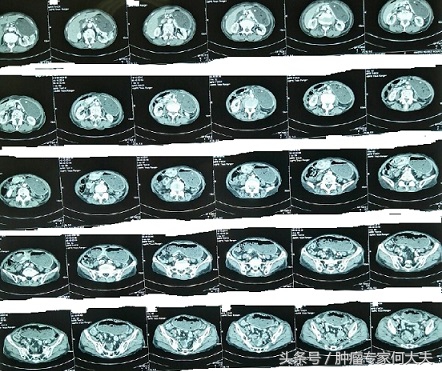

农村老人吃了吐,吐了再吃,坚持不了才就医,一查竟是胃癌晚期 随着时间推移,原本清瘦的阿嬷越来越消瘦了,体力明显下降,再也不能像一年前从玉米地里挑些包谷米回家。国庆期间,在外打工的小儿子回到家里,知道母亲生病了,就带她去医院检查,在医院里医生给做了上腹部CT,结果甚为厉害,严重胃储留,时间长了胃扩张厉害,本来小小的胃,现在变得满肚子都是胃,下界到了盆腔。由于不停呕吐,医生给下了胃管,负压引流,胃胀呕吐明显减轻。